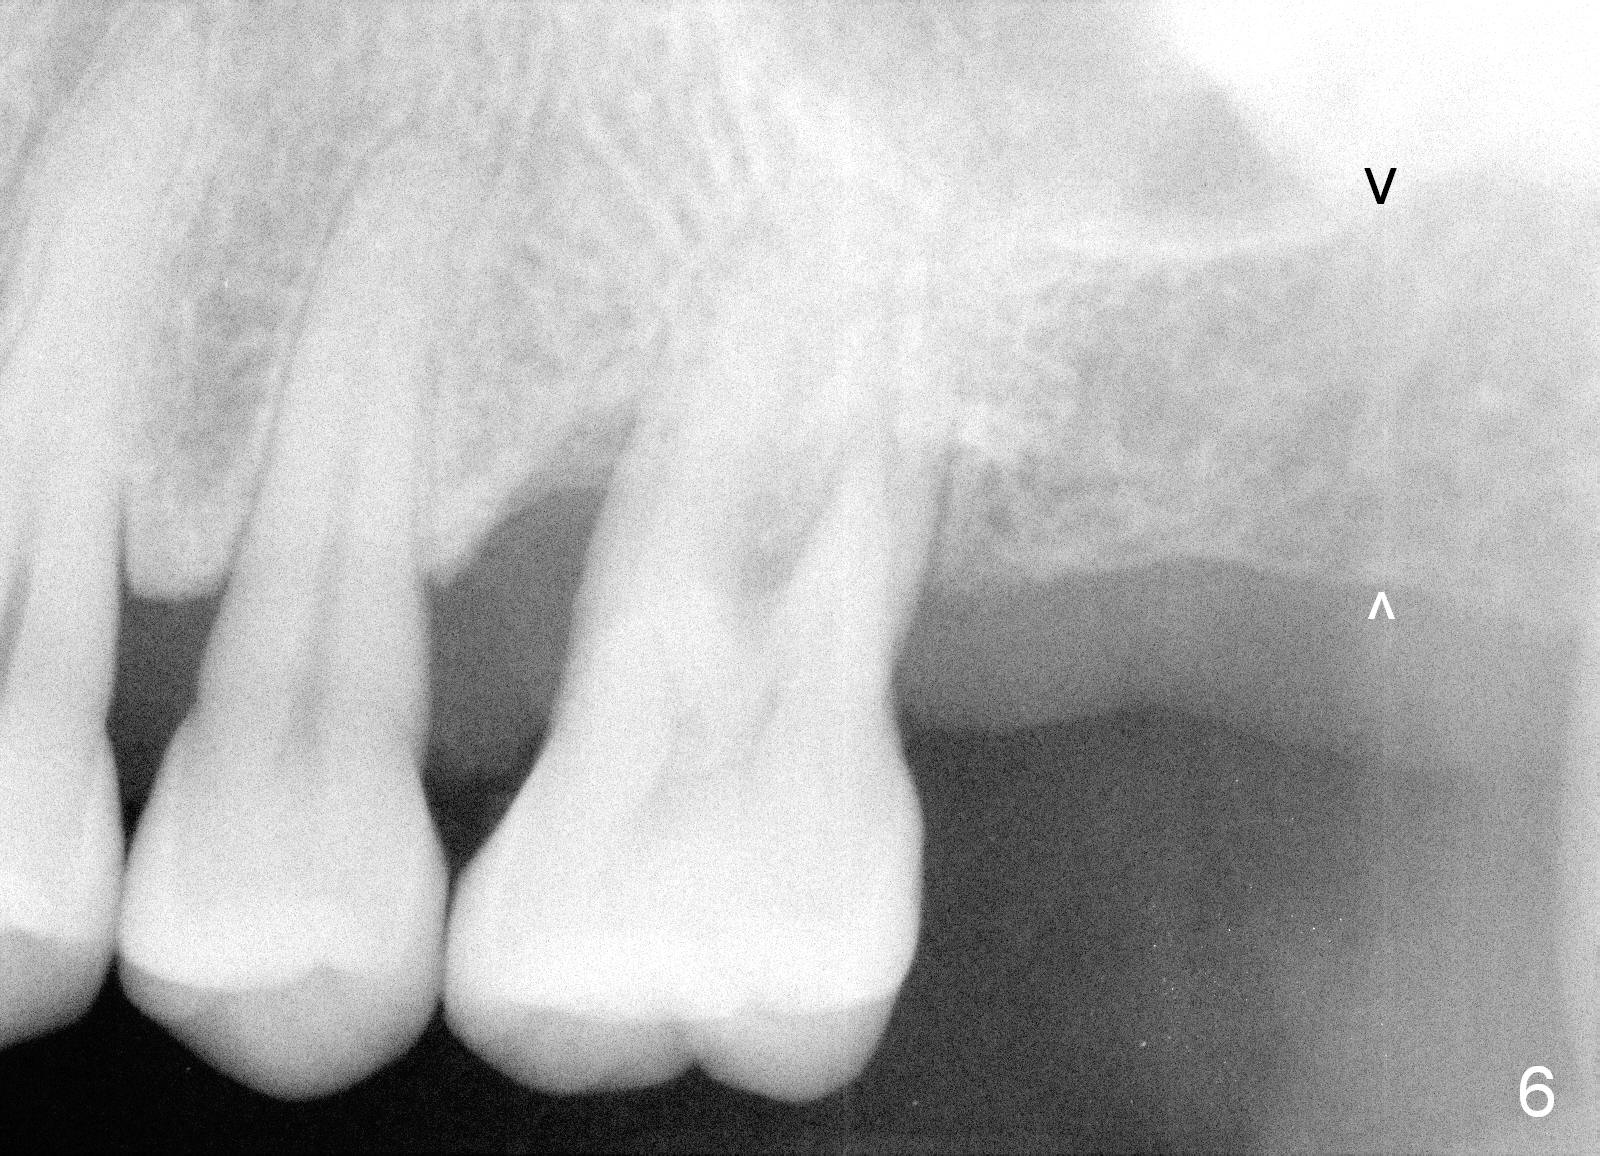

When she returns 7 years later, the tooth #2 has perio abscess with severe bone loss (Fig.3). She refuses to take antibiotic for infection control, but agrees to have immediate implant for #2 because of 1-staged surgery (Fig.5 I: 8x17 mm; A: abutment; P: bone powder (graft)). She is aware of delayed implants at the sites of #15 and 31 later. The bone height at the site of #15 reduces from 12 mm (Fig.4) to 7 mm (Fig.6) in 7 years.